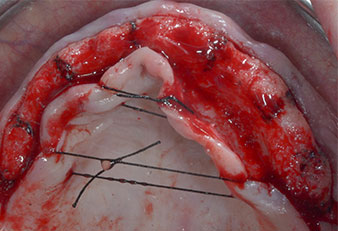

Due to the relatively hard bone (D2) in this area, the 10 mm long implant sites at positions 11 and 21 were finalized with a 4 mm diameter rotary drill, in combination with a W&H WS-75 L surgical contra-angle handpiece, the W&H Implantmed implant motor and the optional W&H Osstell ISQ module. In contrast, due to the soft bone the posterior sites were prepared to a final 3 mm diameter using the Piezomed I3P instrument. The implants were finally placed transgingivally to osseointegrate for three months (Figs. 6-10). The existing denture was retained on four provisional implants (Fig. 8).

10-mm tissue level implant

Fig. 6: A 10-mm tissue level implant is placed at position 21. The implant at position 11 and the three left posterior 4-mm implants are already in place.

Implant stability

Fig. 7: Implant stability is determined with a SmartPeg and the W&H Osstell ISQ module. All values are in the medium to high range, with a minimum of ISQ 69.

Provisional implants

Fig. 8: After fixation of the gingiva formers provisional implants are placed at positions 18, 12, 22 and 28.